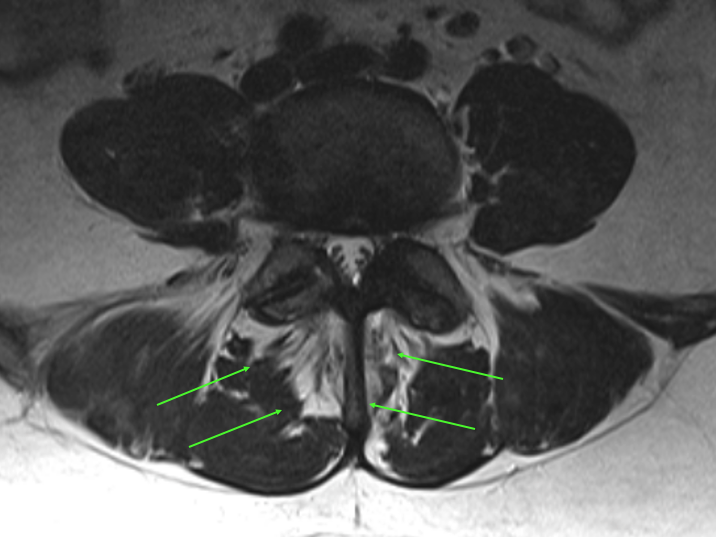

Physiological Healing of Radial and Concentric Discal (Annular) Fissures